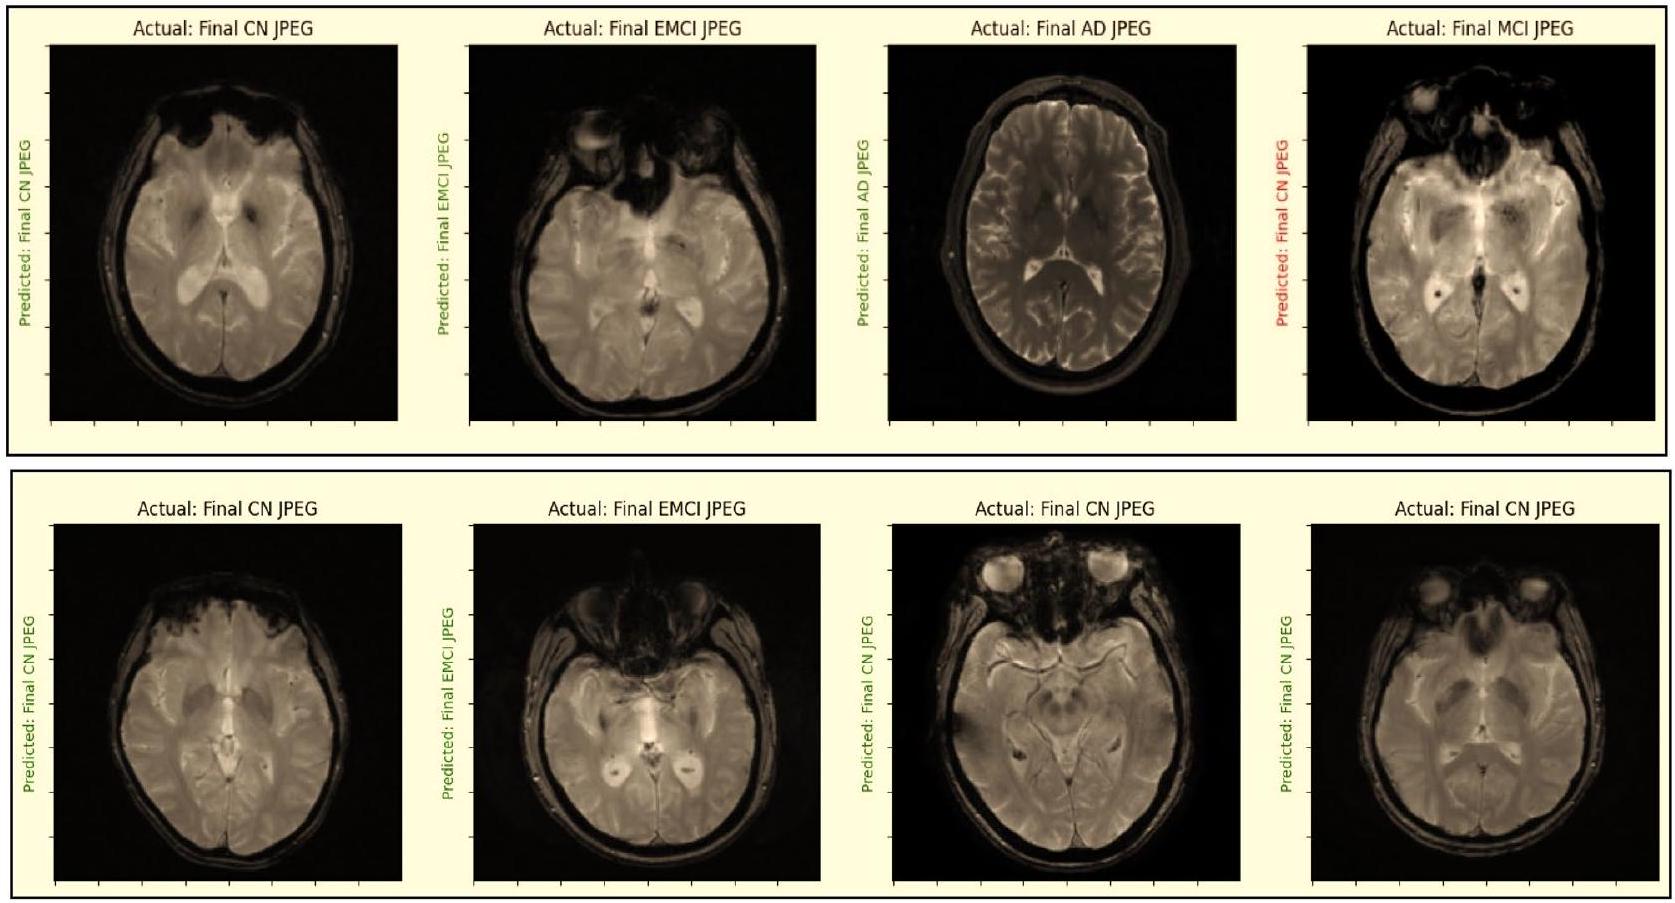

In this section, the authors detail the experimental methodology and results of their study on a combined convolutional neural network (CNN) model applied to MRI data from the Alzheimer’s Disease Neuroimaging Initiative (ADNI). The dataset was augmented using the ADASYN technique to address data imbalance, resulting in a total of 3,000 images. The data was then partitioned into training, validation, and test sets. The proposed model integrates two distinct CNNs, which were trained on a 5-way multiclass MRI dataset. Performance metrics, including accuracy, recall, precision, balanced accuracy, Matthew’s correlation coefficient, and loss function, were employed to evaluate the individual and combined network performances.

The findings indicate that reducing filter size can enhance classification results; specifically, CNN2, which utilizes a $5 \times 5$ filter, requires double the number of filters compared to CNN1, which employs a $3 \times 3$ filter, to achieve similar accuracy. Notably, the combined network outperformed both individual networks, demonstrating improved accuracy due to the complementary nature of the two models. The effectiveness of this combined approach was further validated across various classification tasks, including benchmark three-way, four-way, and five-way multiclass problems, with performance metrics summarized in Table 8 and visualized in Figure 6, which illustrates training versus validation accuracy and loss across the different classification challenges.

The discussion section of the research paper highlights the effectiveness of a proposed model for the early detection of Alzheimer’s disease (AD) using MRI data. The model, which integrates two convolutional neural networks (CNNs) concatenated in a classification layer, demonstrates superior performance in distinguishing between various stages of AD, including mild cognitive impairment (MCI) and healthy controls (CN). The results indicate that the proposed method outperforms existing models in terms of accuracy across three-way, four-way, and five-way multiclass classifications, as evidenced by comparative analyses with previously published studies.